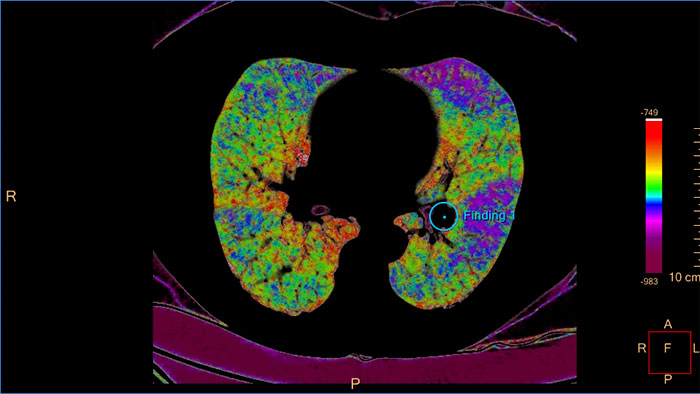

Assessing lung nodules over time

Enables review and analysis of thoracic CT images, providing segmentation, quantification and characterization of physician-indicated lung nodules. The application can be used in both diagnostic and screening evaluations, supporting Low Dose CT Lung Cancer Screening*